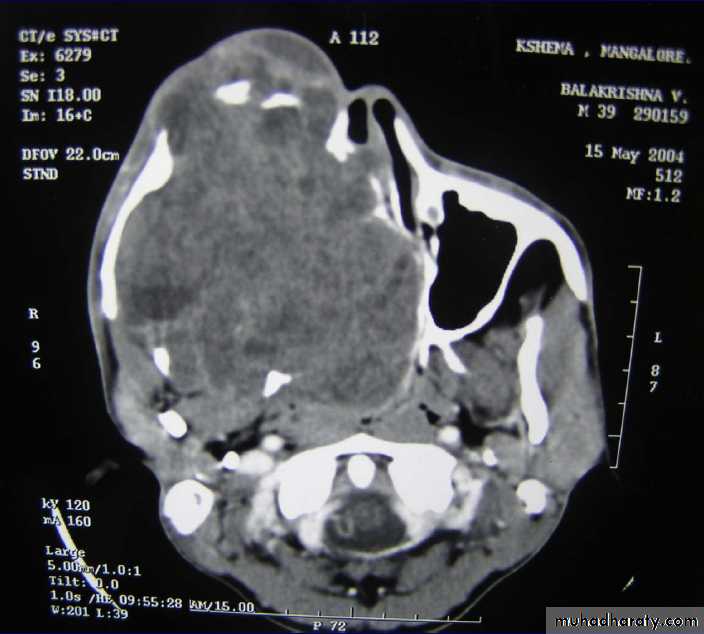

Axial CT shows radiopaque mass oblitearating maxillary sinus and nasalcavity on the right sideAmeloblastoma(ADAMANTINOMA)

DIAGNOSIS:X-ray PNS.

CT Scan of PNS ( Coronal & Axial).